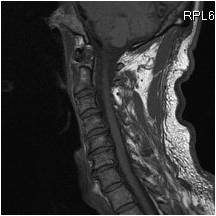

Back injury mechanisms

If you are limited by musculoskeletal symptoms, there will be impairment in your ability to deliver your professional skills. This will slowly lead to a reduction in confidence and burn out sets in. The MRI scan shows a middle aged dentist who has significant cervical disc degeneration affecting the C567 region resulting in upper limb neuropathy. The practise of dentistry is completely impaired as the practitioner cannot work without the symptoms of pain and altered dexterity occurring. Fig 1

happy_backs_1The tissue bio-mechanics of tissue creep from poor posture (postural, work related) will finally result in the spinal tissues failing at the segment where they have been subjected to this level of strain. In dentistry, one vulnerable area is the neck region where poor posture has occurred due to the operator concentrating on performing with direct vision. Fig 2